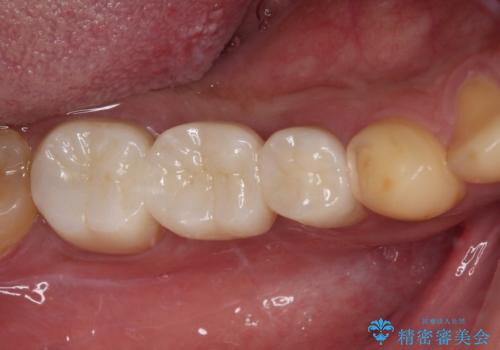

部分矯正を併用した奥歯のインプラント治療